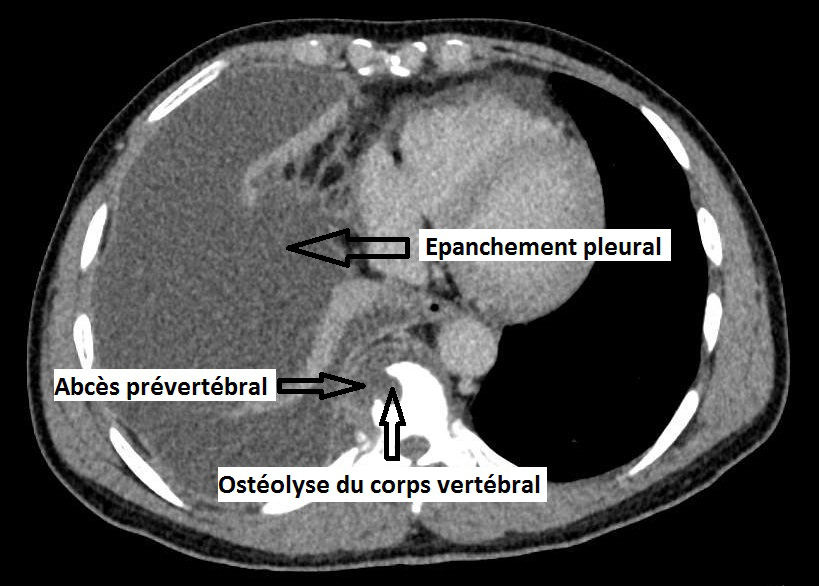

Il faut donc évoquer une pathologie rachidienne inflammatoire/infectieuse/tumorale avec syndrome de compression médullaire partiel se traduisant uniquement par une claudication médullaire : celle-ci correspond à un syndrome pyramidal, démasqué par l’effort.